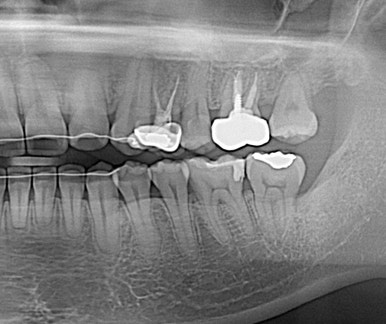

Case details

사랑니 교정

사랑니를 교정치료를 통해 어금니로 사용하는 케이스